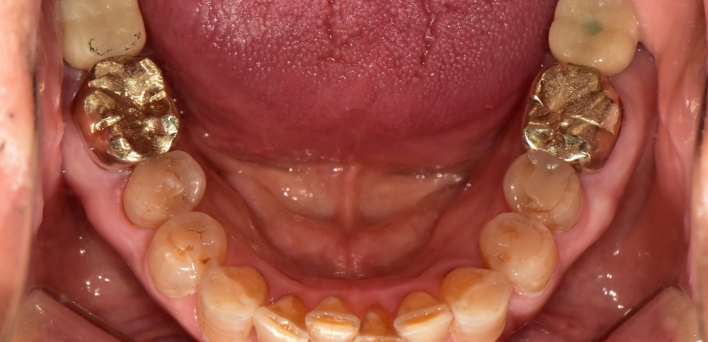

임플란트 : 손 ** 님 (50대)

Before Before

2020.02.30

환자 특징01무치악 상태

환자 특징02수년간 무치악으로 지내심

임플란트가 불가능할것이라

생각하고 내원

위, 아래 6개씩 식립

디지털 풀아치 임플란트